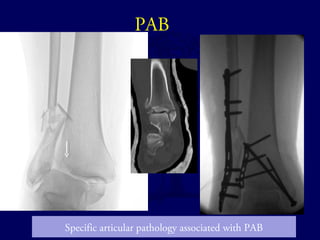

PAB

Specific articular pathology associated with PAB